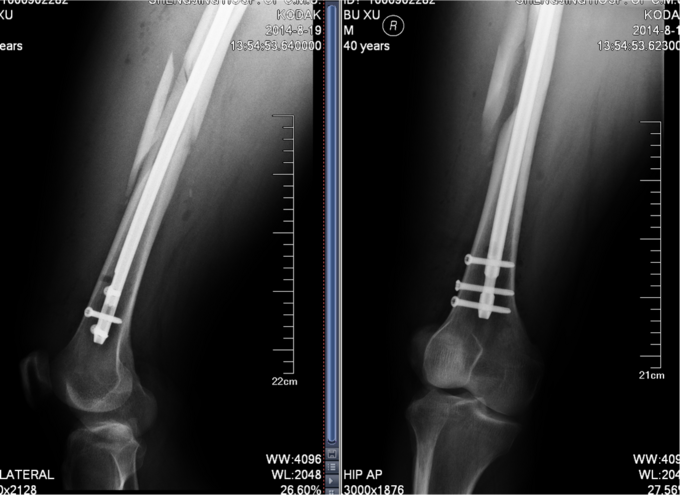

患者于2014-8-14 13:30左右,工作时不慎被重物砸伤,当时无法站立,自觉头晕,意识清楚,自觉大腿部疼痛,无法活动,被急送往我院急诊,经检查诊断为“右股骨干骨折”,给予对症处置,并请我科会诊,现患者为进一步诊治,转入我科病房,我科以“右股骨干骨折”为诊断收入院,患者伤后无昏迷,无恶心呕吐,无呼吸困难,至今未排便排气

右大腿肿胀,活动受限,压痛(+),骨擦音(+),骨擦感(+),可见异常活动,患肢皮肤感觉较健侧未见明显异常;足趾活动灵活,肌力正常,末梢循环可,足背动脉可触及。

诊断:右股骨干骨折 患者入院后急诊行右胫骨结节骨骼牵引术,术后维持患者长度,减轻患者疼痛,完善相关检查后,行右股骨干骨折闭合复位髓内针内固定术。